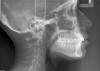

Force Опубликовано 5 октября, 2011 Поделиться Опубликовано 5 октября, 2011 Удаление 18 28 38 48. Снятие брекетов. Кондилография. Анализ окклюзии в артикуляторе. Определение терапевтической позиции на шине. Стабилизация челюсти. Лечение на вестибулярной брекет-системе на многопетлевой технике (MEAW). Такова тактика ведения пациентов с дисфункцией ВНЧС (что у вас в полном объеме, судя по стертым головкам сустава). Ссылка на комментарий

Makeit Опубликовано 5 октября, 2011 Автор Поделиться Опубликовано 5 октября, 2011 Удаление 18 28 38 48. Снятие брекетов. Кондилография. Анализ окклюзии в артикуляторе. Определение терапевтической позиции на шине. Стабилизация челюсти. Лечение на вестибулярной брекет-системе на многопетлевой технике (MEAW). Такова тактика ведения пациентов с дисфункцией ВНЧС (что у вас в полном объеме, судя по стертым головкам сустава).Тоесть вы считаете, что в добавок к краниальному искажению у сеня ещё и дисфункция ВНЧС? А лечение в этих случаях не совпадают? Когда я открываю рот то нижняя желюсть идет не по прямой, как-то всторону сначала( не сильно) а потом прямо встаёт. Ссылка на комментарий

Makeit Опубликовано 5 октября, 2011 Автор Поделиться Опубликовано 5 октября, 2011 Сложно со слов комментировать, только после непосредственного осмотра и диагностики можно с уверенностью сказать, что происходит не так... Мне совсем не понятно, например, для чего и как там 8-ки перемещают?Тактика была выбрана такая: просто переместить верхний зубной ряд до совмещения центральной оси с нижним зубным рядом, т.к мне было сказано что моя проблема кроется именно в зубах а не в челюсти (что тоже предпологалось, но после ортопантомограммы, почиму-то,исключилось). Вот, и начали сдвигать по одному зубу начиная с 18 назад. Ссылка на комментарий

Skip Опубликовано 5 октября, 2011 Поделиться Опубликовано 5 октября, 2011 Тактика была выбрана такая: просто переместить верхний зубной ряд до совмещения центральной оси с нижним зубным рядом, т.к мне было сказано что моя проблема кроется именно в зубах а не в челюсти (что тоже предпологалось, но после ортопантомограммы, почиму-то,исключилось). Вот, и начали сдвигать по одному зубу начиная с 18 назад. По ОПТГ тех нарушений, о которых я говорил, не определить, только в артикуляторе, причём можно в мм вычислить, сколько на уровне зубов, а сколько на краниальном уровне. Ссылка на комментарий

Makeit Опубликовано 5 октября, 2011 Автор Поделиться Опубликовано 5 октября, 2011 По ОПТГ тех нарушений, о которых я говорил, не определить, только в артикуляторе, причём можно в мм вычислить, сколько на уровне зубов, а сколько на краниальном уровне.Но вы же как-то предположили что у меня именно то что вы сказали?По моей ОПТГ даже я заметила что у меня с верхней челюстью каки-то проблемы, и как мне показалось, не связанные с зубами. Ссылка на комментарий

Skip Опубликовано 5 октября, 2011 Поделиться Опубликовано 5 октября, 2011 Но вы же как-то предположили что у меня именно то что вы сказали? По моей ОПТГ даже я заметила что у меня с верхней челюстью каки-то проблемы, и как мне показалось, не связанные с зубами. Да я тоже заметил на ОПТГ , хотя использую для этого специфическую, более достоверную диагностику, да и 10 лет практики, в этом направлении, сказывается Ссылка на комментарий